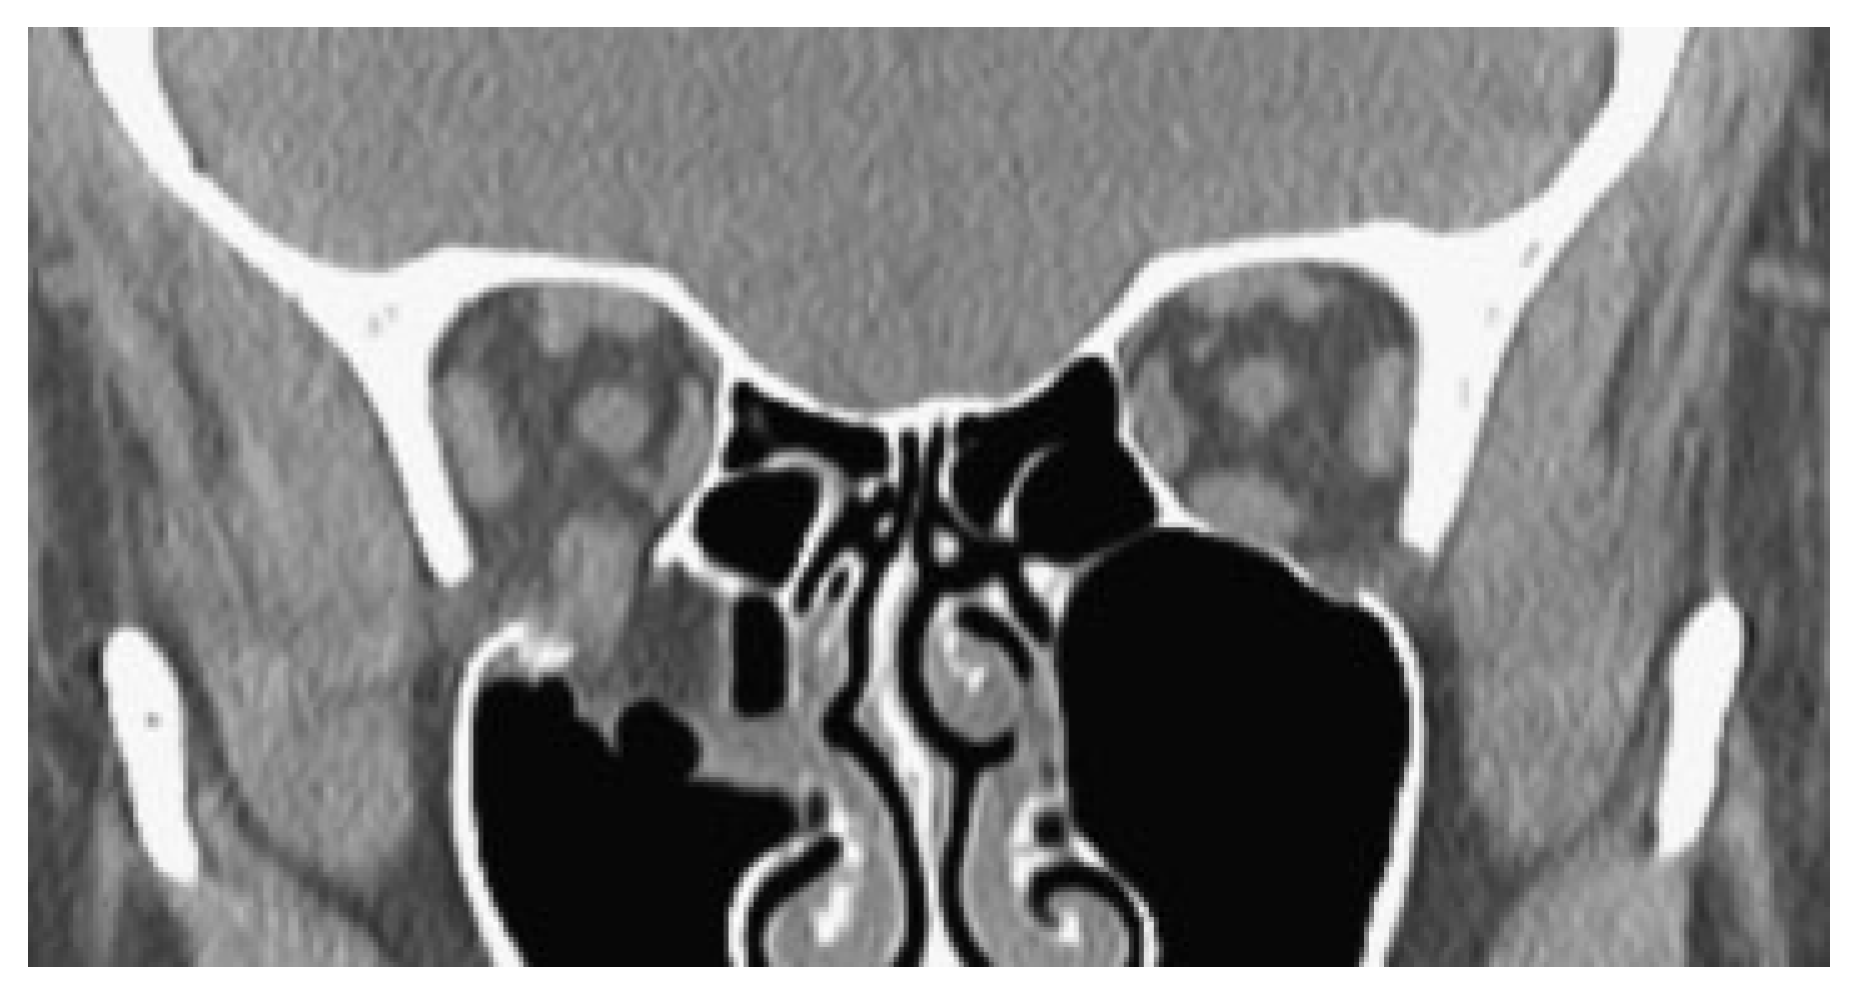

Noncontrast orbital CT scan demonstrated a comminuted left orbital floor fracture and an associated minimally displaced fracture of the left lamina papyracea and nasal bones. The shape of the inferior rectus muscle was distorted vertically and it appeared to be partially entrapped in the orbital floor fracture (Figure 2).

In this patient, a large orbital floor and medial wall fracture was present. Although the anterior portion was classically displaced, the posterior portion of the floor was atypically nondisplaced. Consequently, posterior portions of the left inferior rectus muscle and sheath became caught between two nondisplaced bone fragments (Figure 2, red arrows) and clinically evident extraocular muscle entrapment was seen. While entrapment through a nondisplaced fracture is rare in adults, this should be differentiated from herniation of orbital tissue in a displaced fracture, which is common. In herniation, there is no strangulation of muscle tissue and the risks of muscle damage, necrosis, or the OCR are lower. Occasionally when muscle or perimuscular tissue is herniated, limitation of gaze can be manifest clinically and a distortion of the shape of the inferior rectus can be observed radiographically [6] (Figure 7).

Figure 2. Computed tomography of a left partially displaced orbital floor fracture and nondisplaced medial wall fracture with prominent her- niation of orbital fat through the defect centrally and posterior entrapment of the inferior rectus muscle in nondisplaced fracture elements (red arrows).